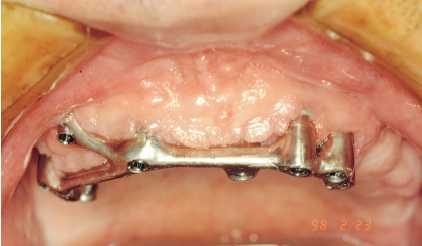

Figura 1. Paciente con acúmulo

de cálculo y placa, bolsas

periimplantarias y movilidad de

los implantes